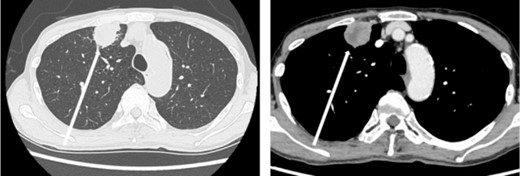

The patient was a 73-year-old man. He had a history of arteriosclerosis obliterans in the lower extremities, transient atrial fibrillation, and was consuming two antiplatelet agents. The patient had a fever within the range of 38°C. Blood tests showed an elevated white blood cell (WBC) count of 31.6 × 103/μl (neutrophil, 90.2%), CRP of 9.67 mg/dl, and APTT of 125.4 s. Chest radiography revealed an abnormal shadow in the upper lobe of the right lung (Fig. 1). Contrast-enhanced chest CT revealed an irregularly shaped mass, 43 × 33 × 28 mm in size, in the upper lobe of the right lung (Fig. 2). 18F-fluorodeoxyglucose-positron emission tomography showed abnormal accumulation with a maximum standardized uptake value of 28.4 in a pointed lesion in the upper lobe of the right lung (Fig. 3). A bronchoscopic biopsy was performed, and the patient was diagnosed with non-small cell carcinoma.

Chest computed tomography (CT) findings. An irregular mass 43 × 33 × 28 mm in size was found in the upper lobe of the right lung, which was suspected to be primary lung cancer.

18F-fluorodeoxyglucose positron emission tomography findings. Abnormal accumulation of Max SUV 28.4 was found in a pointed lesion in the right upper lobe of the lung, which was considered to be a primary lung cancer site.